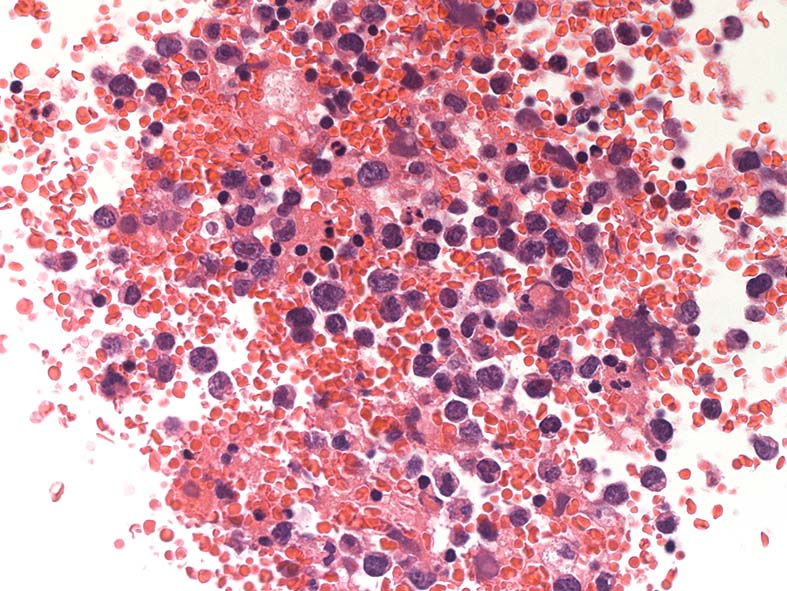

心タンポナーデの診断で心嚢液穿刺ドレナージ. 心嚢液内に多数の異型細胞増加が認められた.心嚢液smear標本. Giemsa染色

小型リンパ球の3-4倍, 空胞の多い青色調の細胞質をもった大型異型細胞が増殖. 核クロマチンは微細顆粒状, 繊細で核小体が1-数個認められる. 二核の異型細胞がある.

ALL-L3やBurkittリンパ腫細胞に類似した腫瘍細胞で, 疾患説明のplasmablastsやALKの細胞とは形態が異なって見える.

胸水セルブロック: effusion lymphomaの場合, IHCなどの精査はcell brockで行うことになる.

心嚢水セルブロックHE染色: 小リンパ球の3倍から5倍ほどの大型異型細胞が多数増加している. 核は類円形, くびれをもつ多型核が見られ, クロマチンは微細な傾向. 核小体を1-数個もつ.

N/C比は大. 好酸性の細胞質が認められる. セルブロックでは細胞質空胞はあまりめだたない. high-grade lymphoma疑い.